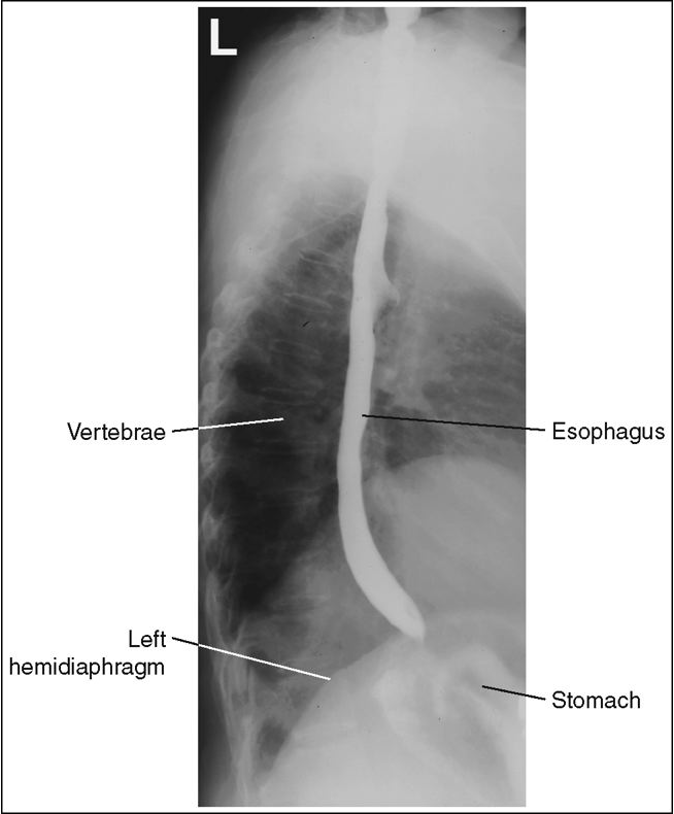

Lateral Esophagus (Right or Left (CR and Positioning)

Recumbent lateral position - preferably right lateral and facing radiographer

Arms forward

MCP centered

Shield patient

Place IR at the top of the mouth

CR at the level of T5-T6

Instruct patient to take big swallows and expose while esophagus is full of barium

Lateral Esophagram Eval Criteria

Arm not interfering with esophagus

Ribs posterior to the vertebrae superimposed with no rotation

Lateral esophagus with proper positioning

Lateral esophagus with superior and middle no barium